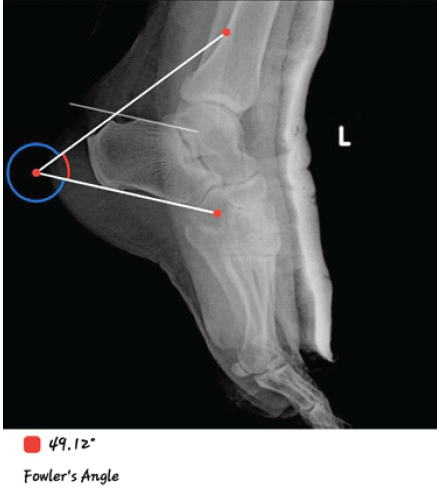

A case series of 10 patients, with 7 female and 3 male patients, with a mean age of 42 years (range 36–50). All patients reported chronic posterior heel pain unresponsive to over 3 months of conservative therapy [3] (Table 1). Radiological confirmation was obtained in each case using Fowler’s angle and presence of parallel pitch lines as shown in Fig. 1 & 2 [1,9].

Figure 1: Post-operative lateral X-ray at 6 months showing restored heel contour and improved angles. Post-op X-ray. Fowler’s angle: 49. American Orthopaedic Foot and Ankle Society at 6 months: 73.